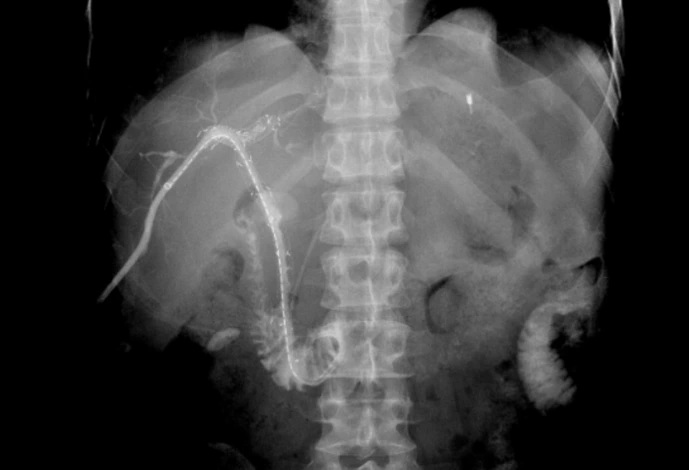

胆道粒子支架是将金属胆道支架与放射性粒子(通常为碘-125,¹²⁵I)相结合的一种创新型介入治疗手段。

粒子支架长期保障胆管通畅

将“减黄”(引流)和“抗肿瘤”(粒子)两种治疗合二为一。通常采用三腔结构,包括一个较大的胆汁引流腔和一到两个较小的粒子腔。

由于造成恶性梗阻的肿瘤会持续生长,导致普通支架或引流管短期内再堵塞。普通支架植入+粒子导管能抑制肿瘤生长,从而显著延长胆道的通畅时间;或者不植入支架,单独使用粒子导管也能起到抑制肿瘤并保持胆管长期通畅。